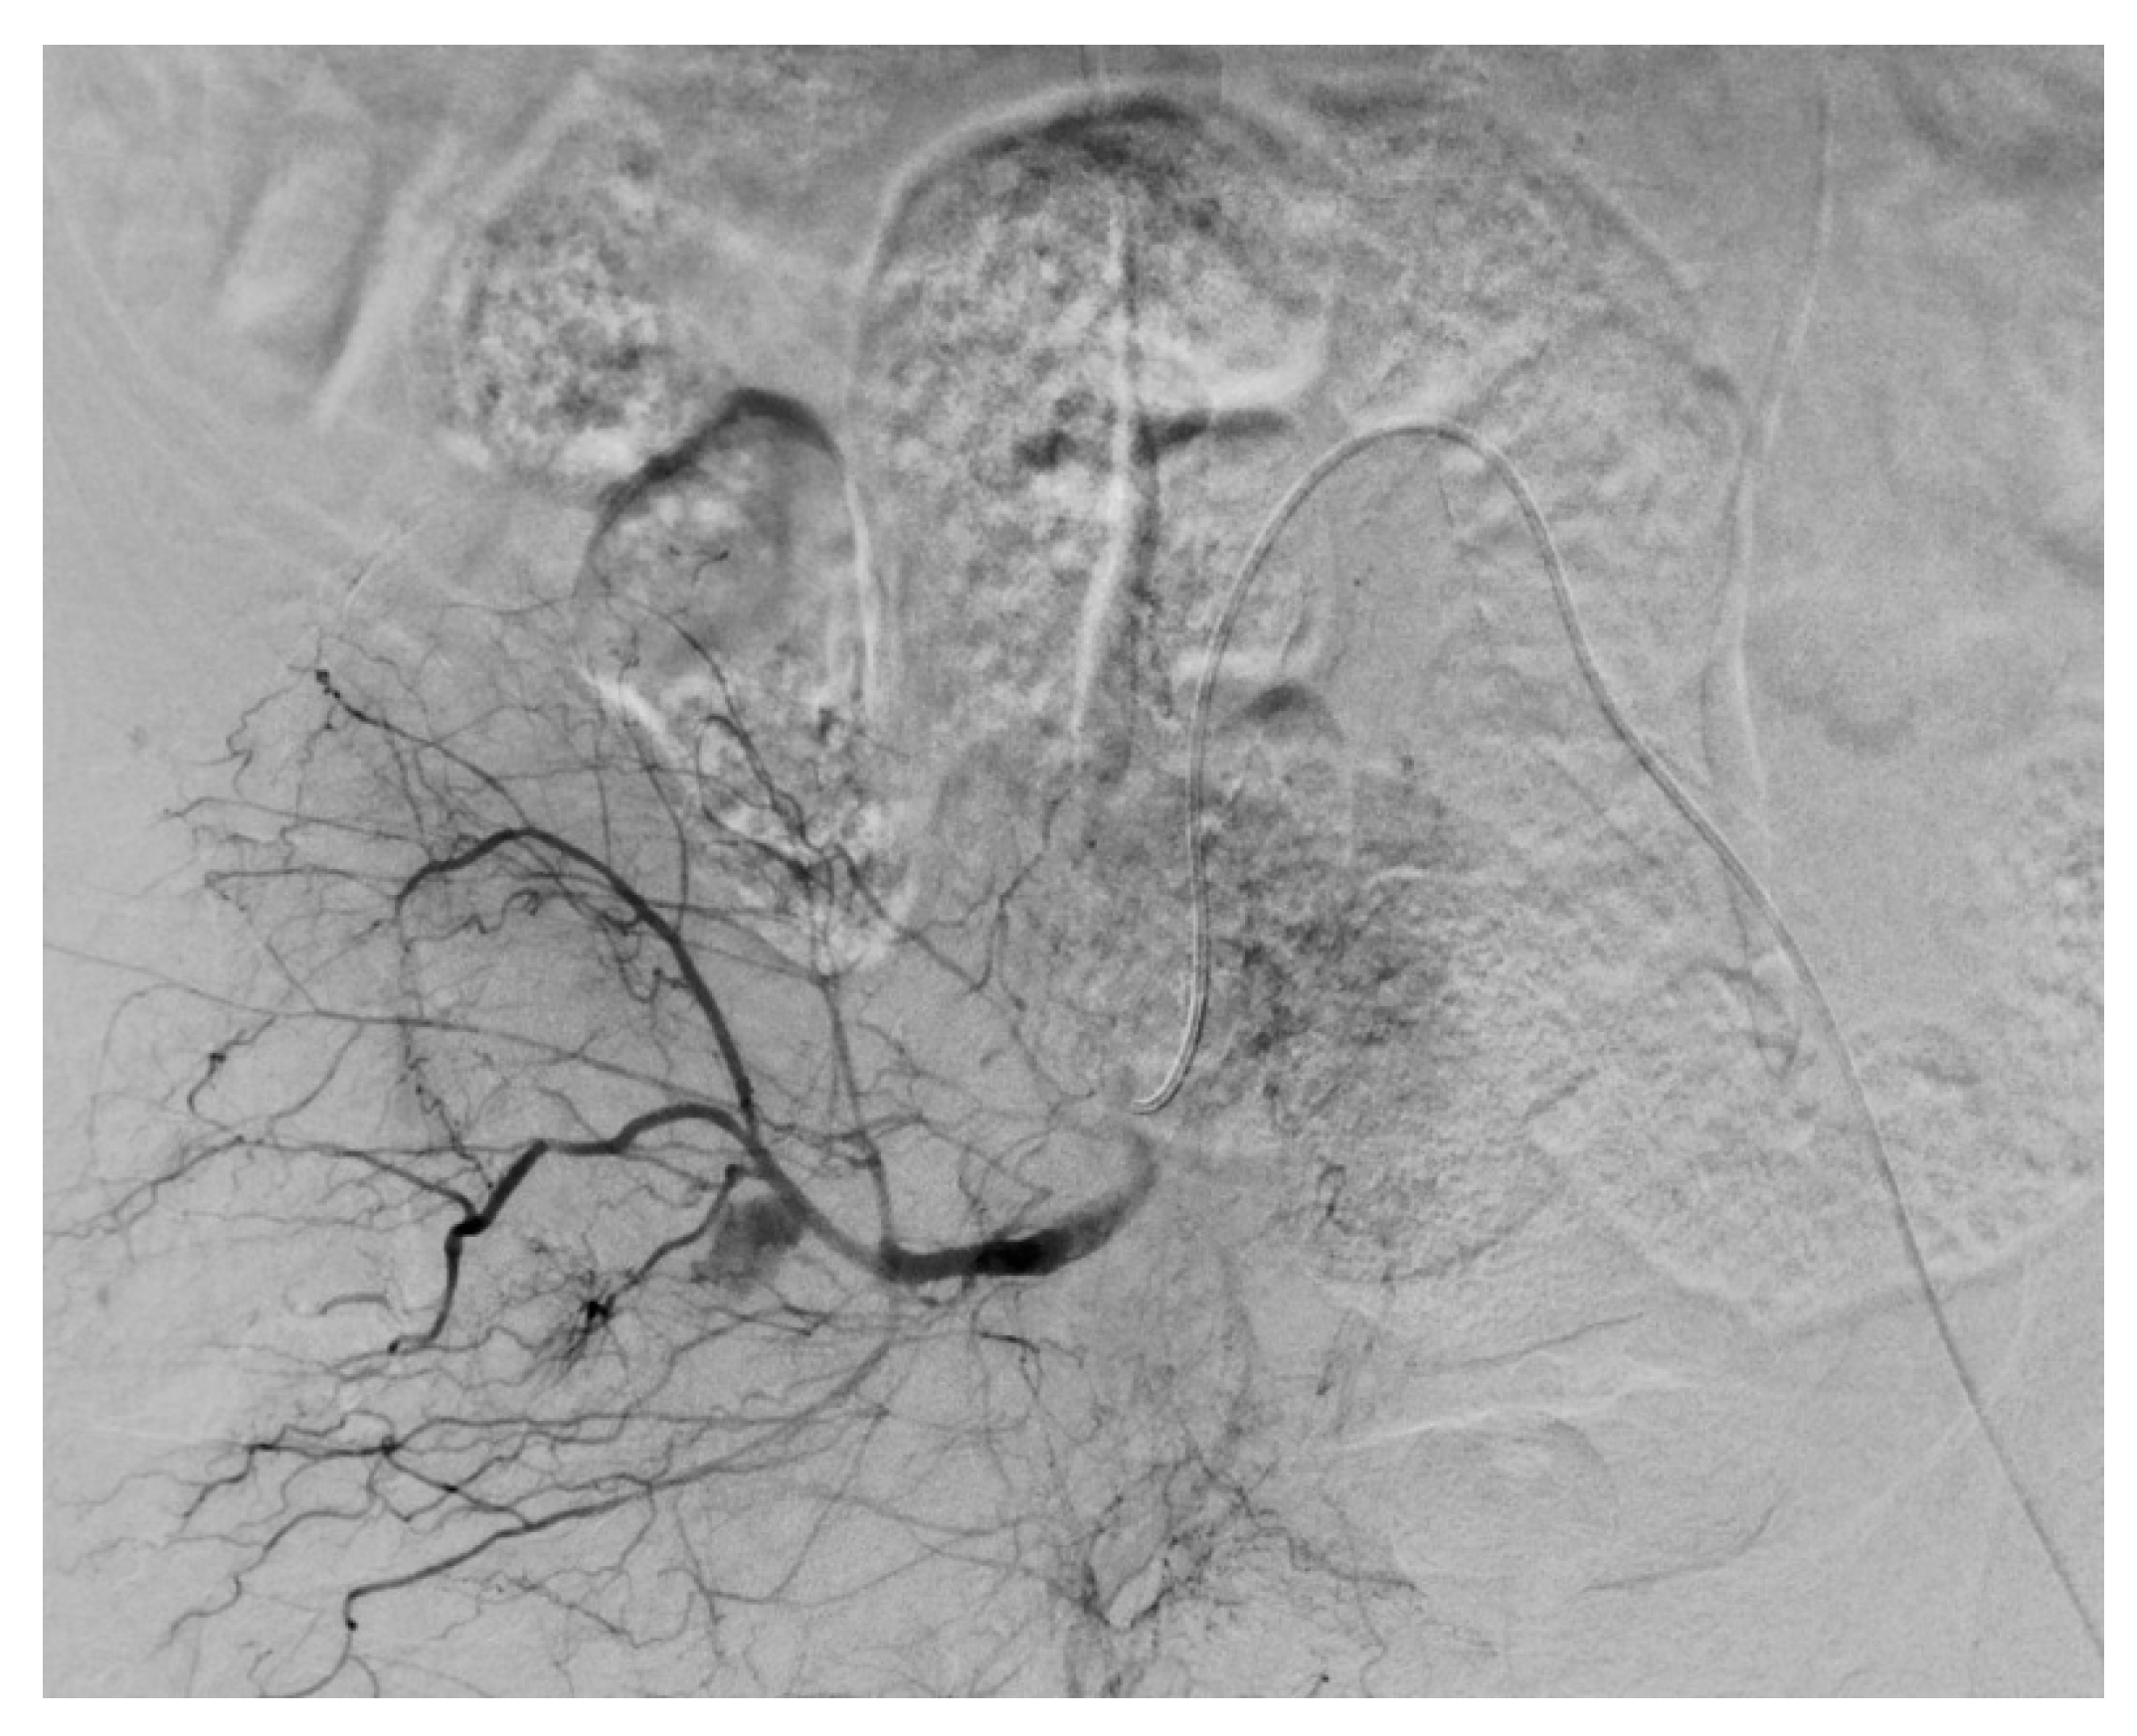

2.5. Procedural Details

- Giurazza, F.; Pane, F.; Roccatagliata, P.; Casciano, E.; Corvino, F.; Festa, P.; Ponticiello, G.; Cappabianca, S.; Romano, L.; Niola, R. Pelvic ring fractures with concomitant large hematomas: Diagnostic investigation with arteriography and eventual embolization in 157 trauma patients, with or without contrast extravasation at emergency CT. Radiol. Med. 2023, 128, 1429–1439. [Google Scholar] [CrossRef] [PubMed]